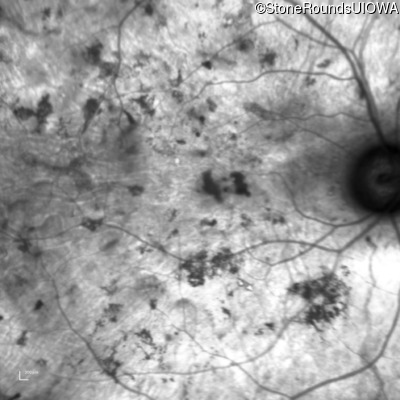

Age at visit: 29 years

Age at visit: 29 years (Visit 2)